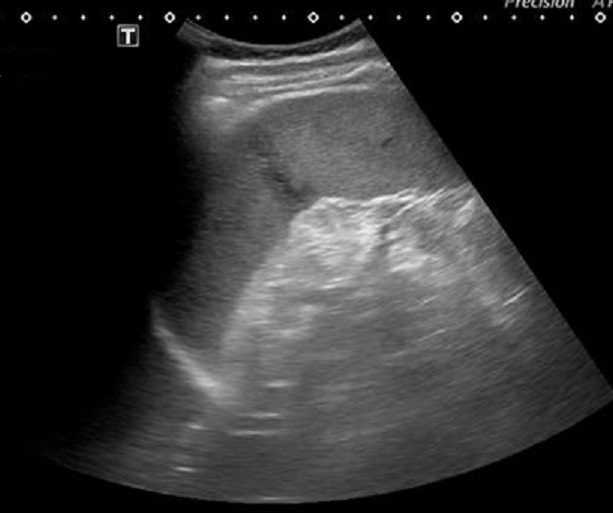

Echographie :

Echographie percutanee de l'abdomen

ou echographie focalisee de l'abdomen ( FAST ) est la

technique de la premiere de l'intention et de choix dans la

traumatisme de la rate . Sur les

traumatisme de la rate de grade agravee souvent en

s'observent de hemoperitoine localisee ou globale , l'absence de fluid intra peritoneale non pas concerne la

rate est normale . Aspect echographique des traumatisme de

la rate est : une augementation de la volume de la rate en

association de la presente de liquide libre et une zone de

mal delimitee sans contour mal de nette . Dans phase aigue le sang

est hypoechogene et puis devient hyperechogene et heterogenes temoinage

de caillaux de la coagulation . A distance on peut

en s'observe des calcification intra et peri-lesionnels .

Dans les traumatismes de la

rate de grade grave de II - V , la signe indirecte

de traumatisme le plus souvent s'observe est image

de hemoperitoine peri-splenique ou globale

intra-peritoneale . Au dessus c'est image de

hemoperitoineale locale peripherique externe de la

rate , c'est une zone de hypoechogene a bien limite

peri-splenique . |

Image

echographique d'une traumatisme de la rate

compliquee avec une hemoperitoine localise

peripherique de la rate . On peut en s'observe de

zone hypoechogenecite a bien limite a inferieure et

a peri-splenique |